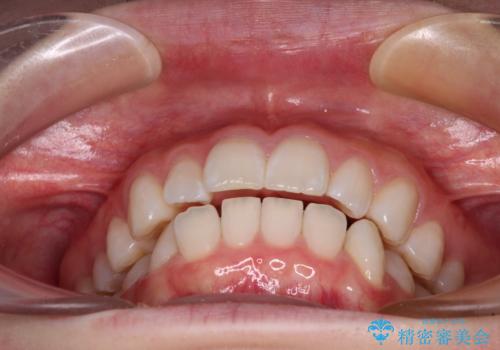

- 前歯の出っ歯と口元の閉じにくさを気にして来院された患者様です。

口元を積極的に引っ込めるために、上下左右の小臼歯4本を抜歯することとしました。

4本の歯を抜歯したことで、飛び出していた口元が引っ込み、横顔が大きく改善されました。